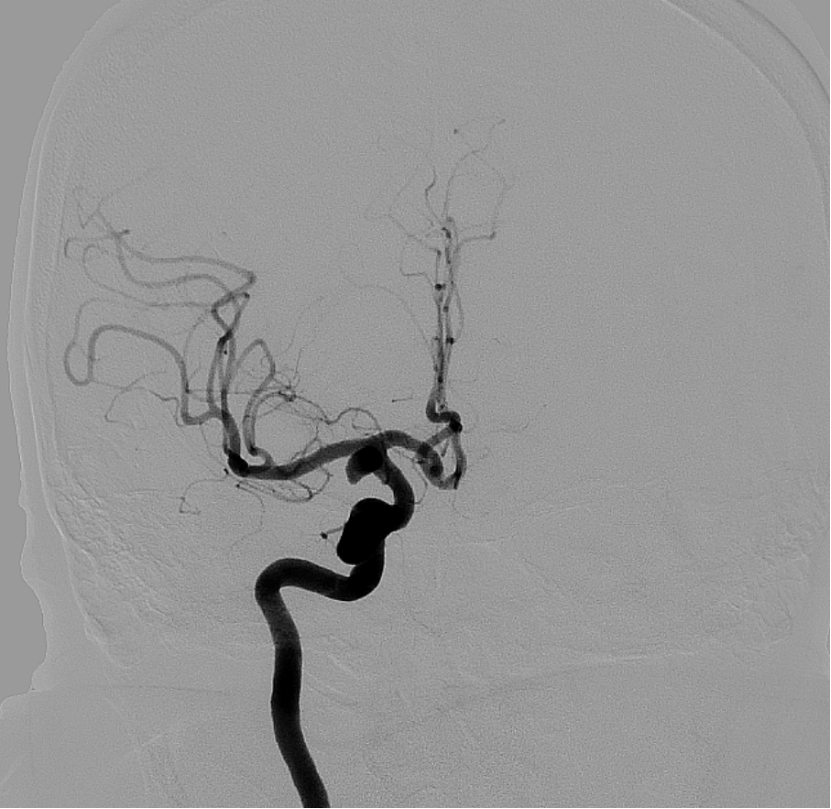

图1 术前造影图

患者取平卧位,麻醉成功后,经右侧股动脉行Seldinger穿刺,置入动脉鞘。随后,使用造影管行全脑血管造影,工作角度造影显示:右侧颈内动脉后交通段动脉瘤,形态不规则、伴子囊。